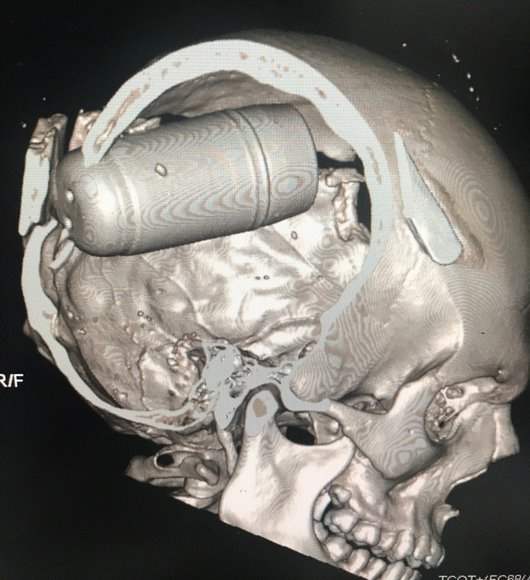

Des analyses par imagerie médicale authentifiées par Amnesty montrent des grenades entièrement encastrées dans le crâne de manifestant·e·s tué·e·s. Les grenades lacrymogènes de 37 millimètres habituellement utilisées par la police à travers le monde « pèsent entre 25 et 50 grammes », d’après Amnesty, mais celles utilisées à Bagdad « pèsent entre 220 et 250 grammes » et leur force est « multipliée par dix » lorsqu’elles sont tirées. De plus, les grenades généralement utilisées sont constituées de plusieurs cartouches plus petites qui se séparent et s’étendent sur une zone donnée. En revanche, les grenades « brise-crâne » à Bagdad consistent en une seule cartouche lourde.

Imagerie médicale d’un patient décédé suite à l’utilisation d’une grenade brise crâne